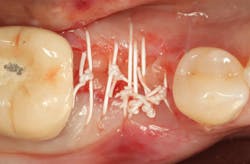

An osteotomy was then created, extending to the apical portion of the split ridge in preparation for implant placement. A bone-level tapered 4.1- x 12-mm implant was placed with a flat cover screw. A mixture of cancellous and cortical allograft particulate was infused with autogenous PRGF and packed around the implant on the mesial and distal aspects. The newly out-fractured buccal plate was positioned intimately adjacent to the buccal portion of the implant, and additional graft material was placed over the buccal plate to further augment the bone horizontally and reduce the risk of buccal-plate resorption during healing. A 25- x 30-mm Ossix Plus membrane was soaked in saline for three minutes and trimmed to extend 3–4 mm beyond the confines of the bone graft and roughly 1 mm from the adjacent teeth.

After the photo was taken to demonstrate the membrane placement, a periosteal elevator was used to further push the membrane under the lingual flap so that it draped intimately over the graft. The partial-thickness flap preparation made during initial incisions allowed for coronal positioning for tension-free primary closure. A CV-5 horizontal mattress suture was used to bring the buccal and lingual flaps together, and closure was completed with interrupted sutures.